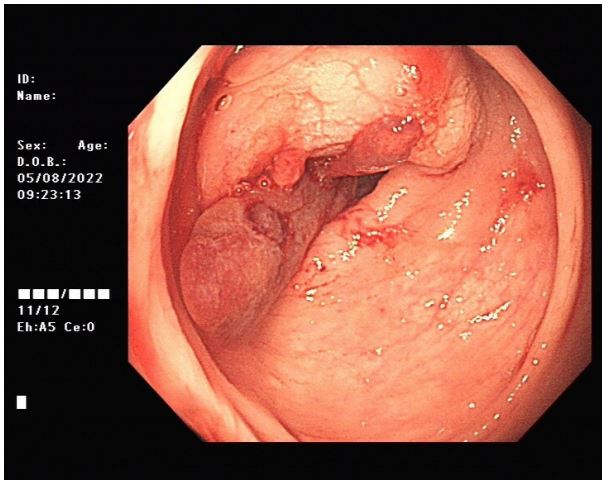

On August 3, 2022 (2-years postoperative), the patient visited the clinic for six months due to anal swelling, the symptoms were not related to menstrual cycle, and a fecal imaging was performed: The distal part of the rectal jug abdomen was seen to be mildly protruding anteriorly during forceful evacuation, with a cystic pouch-like change, about 2.8 cm in length and 0.8 cm in depth. The local intestinal lumen of the sigmoid colon was slightly narrowed, with an upper and lower range of about 3.3 cm, and the margin. The lumen of the sigmoid colon was slightly narrowed, with an upper and lower range of about 3.3 cm, and the margin was not well defined See Figure 1. The intestinal lumen was slightly narrowed, and the endoscope could barely pass through.

Figure 1: Defecography image.